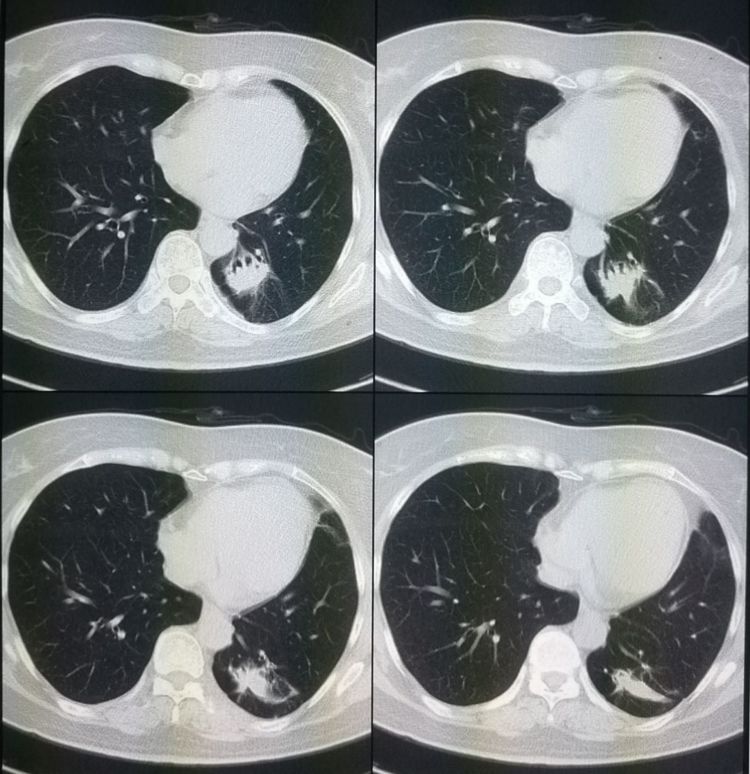

虽然这位患者已经不能手术切除,其它可选择的治疗手段也有很多。患者开始接受化疗,一年后复查病灶明显缩小,转移灶也消失不见了: